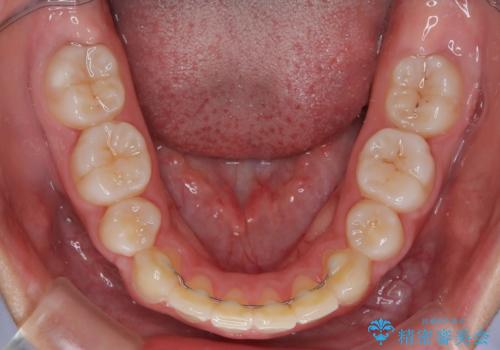

口元の突出感が解消され、睡眠時の口呼吸が改善されました。

- 矯正治療後の保定が不十分だと後戻り(元の位置に戻ろうとする動き)をします